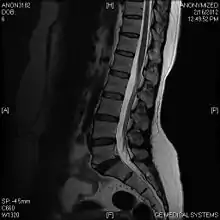

Limbus vertebra

A limbus vertebra is a bone tubercle formed by bone trauma on a vertebral body, bearing a radiographic similarity to a vertebral fracture. The anterior-superior corner of a single vertebra is the common site for this defect although it can also be seen at the inferior corner as well as the posterior or anterior margin. Anatomically, it is assumed to be an intra-vertebral body herniation of the disc material occurring during adolescent growth spurt when the ring apophysis has not yet fused. It was first described by Schmorl in 1927 and later in detail by Leif Sward and Adad Baranto.

Viewed in a lateral radiograph, it appears as a triangular shaped bone fragment, not unlike an anterior lip fracture, but with softer edges.

Limbus vertebra is not always symptomatic, but severe cases may lead to more serious pathological conditions and chronic pain. In rare instances, a posterior limbus vertebra has been described causing radiculopathy due to nerve root compression.